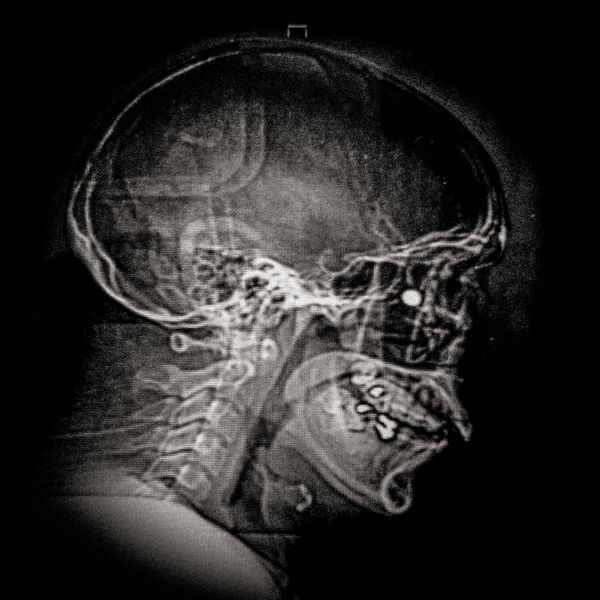

X-ray showing the pellet embedded in the skull of Ybar Soto (29) Ybar was hit by a pellet that lodged in his right eye on October 24, 2019 in Plaza Italia. Santiago. His diagnosis was ocular burst. Santiago, Chile. December 28, 2019

© Cristóbal Olivares - Image from the They are marking us photography project

Ybar Soto (29) Electrical Technician Lives in Puente Alto,Santiago Ybar was hit by a pellet that lodged in his right eye on October 24th, 2019, at Plaza Italia, Santiago. His diagnosis was an eye burst. “If I would have shot the police in his eye, would they have me to signing once a month? I’ve had to face really hard situations, situations where I have seen the police looking at my face and laughing at me, because of the damage they did in my eye. What can I do against that? I can’t do anything. This is a huge anger and pain that is going to weigh me down my whole life. Until now I have the same answer. I do not regret for a fucking second going to protest that day because I am totally and absolutely convinced that we were not doing anything wrong. These are our rights.”